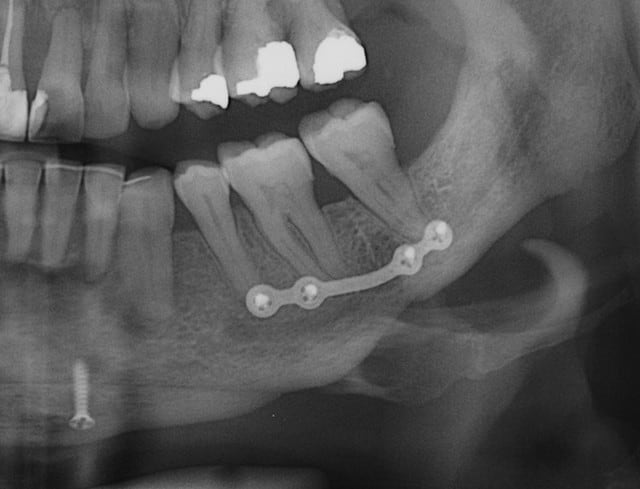

Patiente 58 ans à eu une chirurgie à visée esthétique et "fonctionnelle" adressée pour détartrage en urgence...je ne suis pas spécialiste mais je trouve que la greffe mentonnière est très bof

lésion apicale sur 42 risque de contamination sur la vis en regard..

Nous sommes d'accord pour la chirurgie mais secteur 4 il y a 2mm être là plastie et la mdble, ça ne me fais pas rêver

La chirurgie à 6 mois

Nous sommes d'accord pour la genioplastie je me suis mal exprimé ce qui m'inquiète c'est la proximité de la greffe, pardon genioplastie et de l'infection de 42, d'une part et la mauvaise liaison de la genioplastie secteur 4, mais je suis peut-être pessimiste.

Plusieurs points: les vis de 15mm x 2mm qui transfixent c'est pas top, une seule plaque, qui plus est non réglable de chaque côté, c'est encore moins top. C'est une plaque de fracture.

En mandibulaire gauche c'est quoi ce fil d'osteosynthese? Un troisième fragment? En laissant l'apex de la 48 pile sur le trait d'osteotomie, je dis chapeau.

Pour la lésion de 42, ca peut être lié à la genio. Forage hasardeux? Mais je vote plus pour une lésion endo/paro